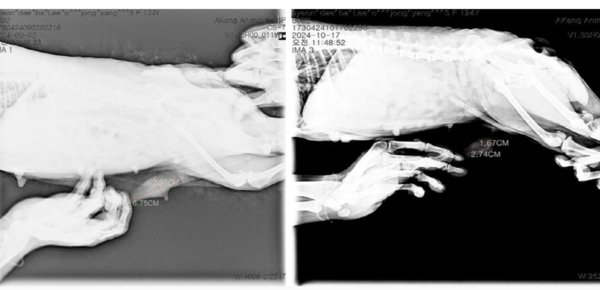

반려견 대상 폴리탁셀 4.5mg/kg 항암효능시험 결과, 유선종양 크기.(좌)투약 전 유선종양 크기(가로 6.75cm-세로 2.92cm), (우)투약 후 유선종양 크기(가로 2.74cm-세로 1.67cm). /현대바이오 제공 반려견 대상 폴리탁셀 4.5mg/kg 항암효능시험 결과, 유선종양 크기.(좌)투약 전 유선종양 크기(가로 6.75cm-세로 2.92cm), (우)투약 후 유선종양 크기(가로 2.74cm-세로 1.67cm). /현대바이오 제공

이번 실험에서는 반려견에게 폴리탁셀의 약물 부작용이 나타나지 않는 최대무독성용량(NOAEL) 이하인 4.5㎎/㎏을 회복기 없이 주 1회씩 3회 연속 투여하고 3주 후에 관찰한 결과, 유선종양 크기가 투약 전보다 무려 76.78% 감소했다. 특히 림프절에 전이된 종양 크기는 투약 전보다 74.01%나 줄어들어 폴리탁셀이 전이암 치료효과도 뛰어남을 입증했다.